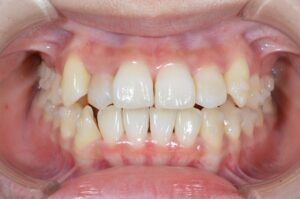

①写真撮影

今の歯並びを色々な角度から撮影します。

せっかくなので矯正前→現在(No.40)で並べてみます。